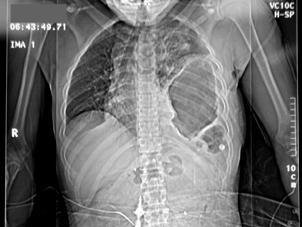

Hemo-pneumotorace stangDetaliu Fracturi costale multiple.Volet costal drept

Fracturi costale multiple Hemitorace drept strivit

Volet costal si hemotorace

drept Fracturi costale multiple

Volet costal si hemotorace drept

Hemitorace drept strivit Hemitorace drept strivit Hemitorace drept strivit